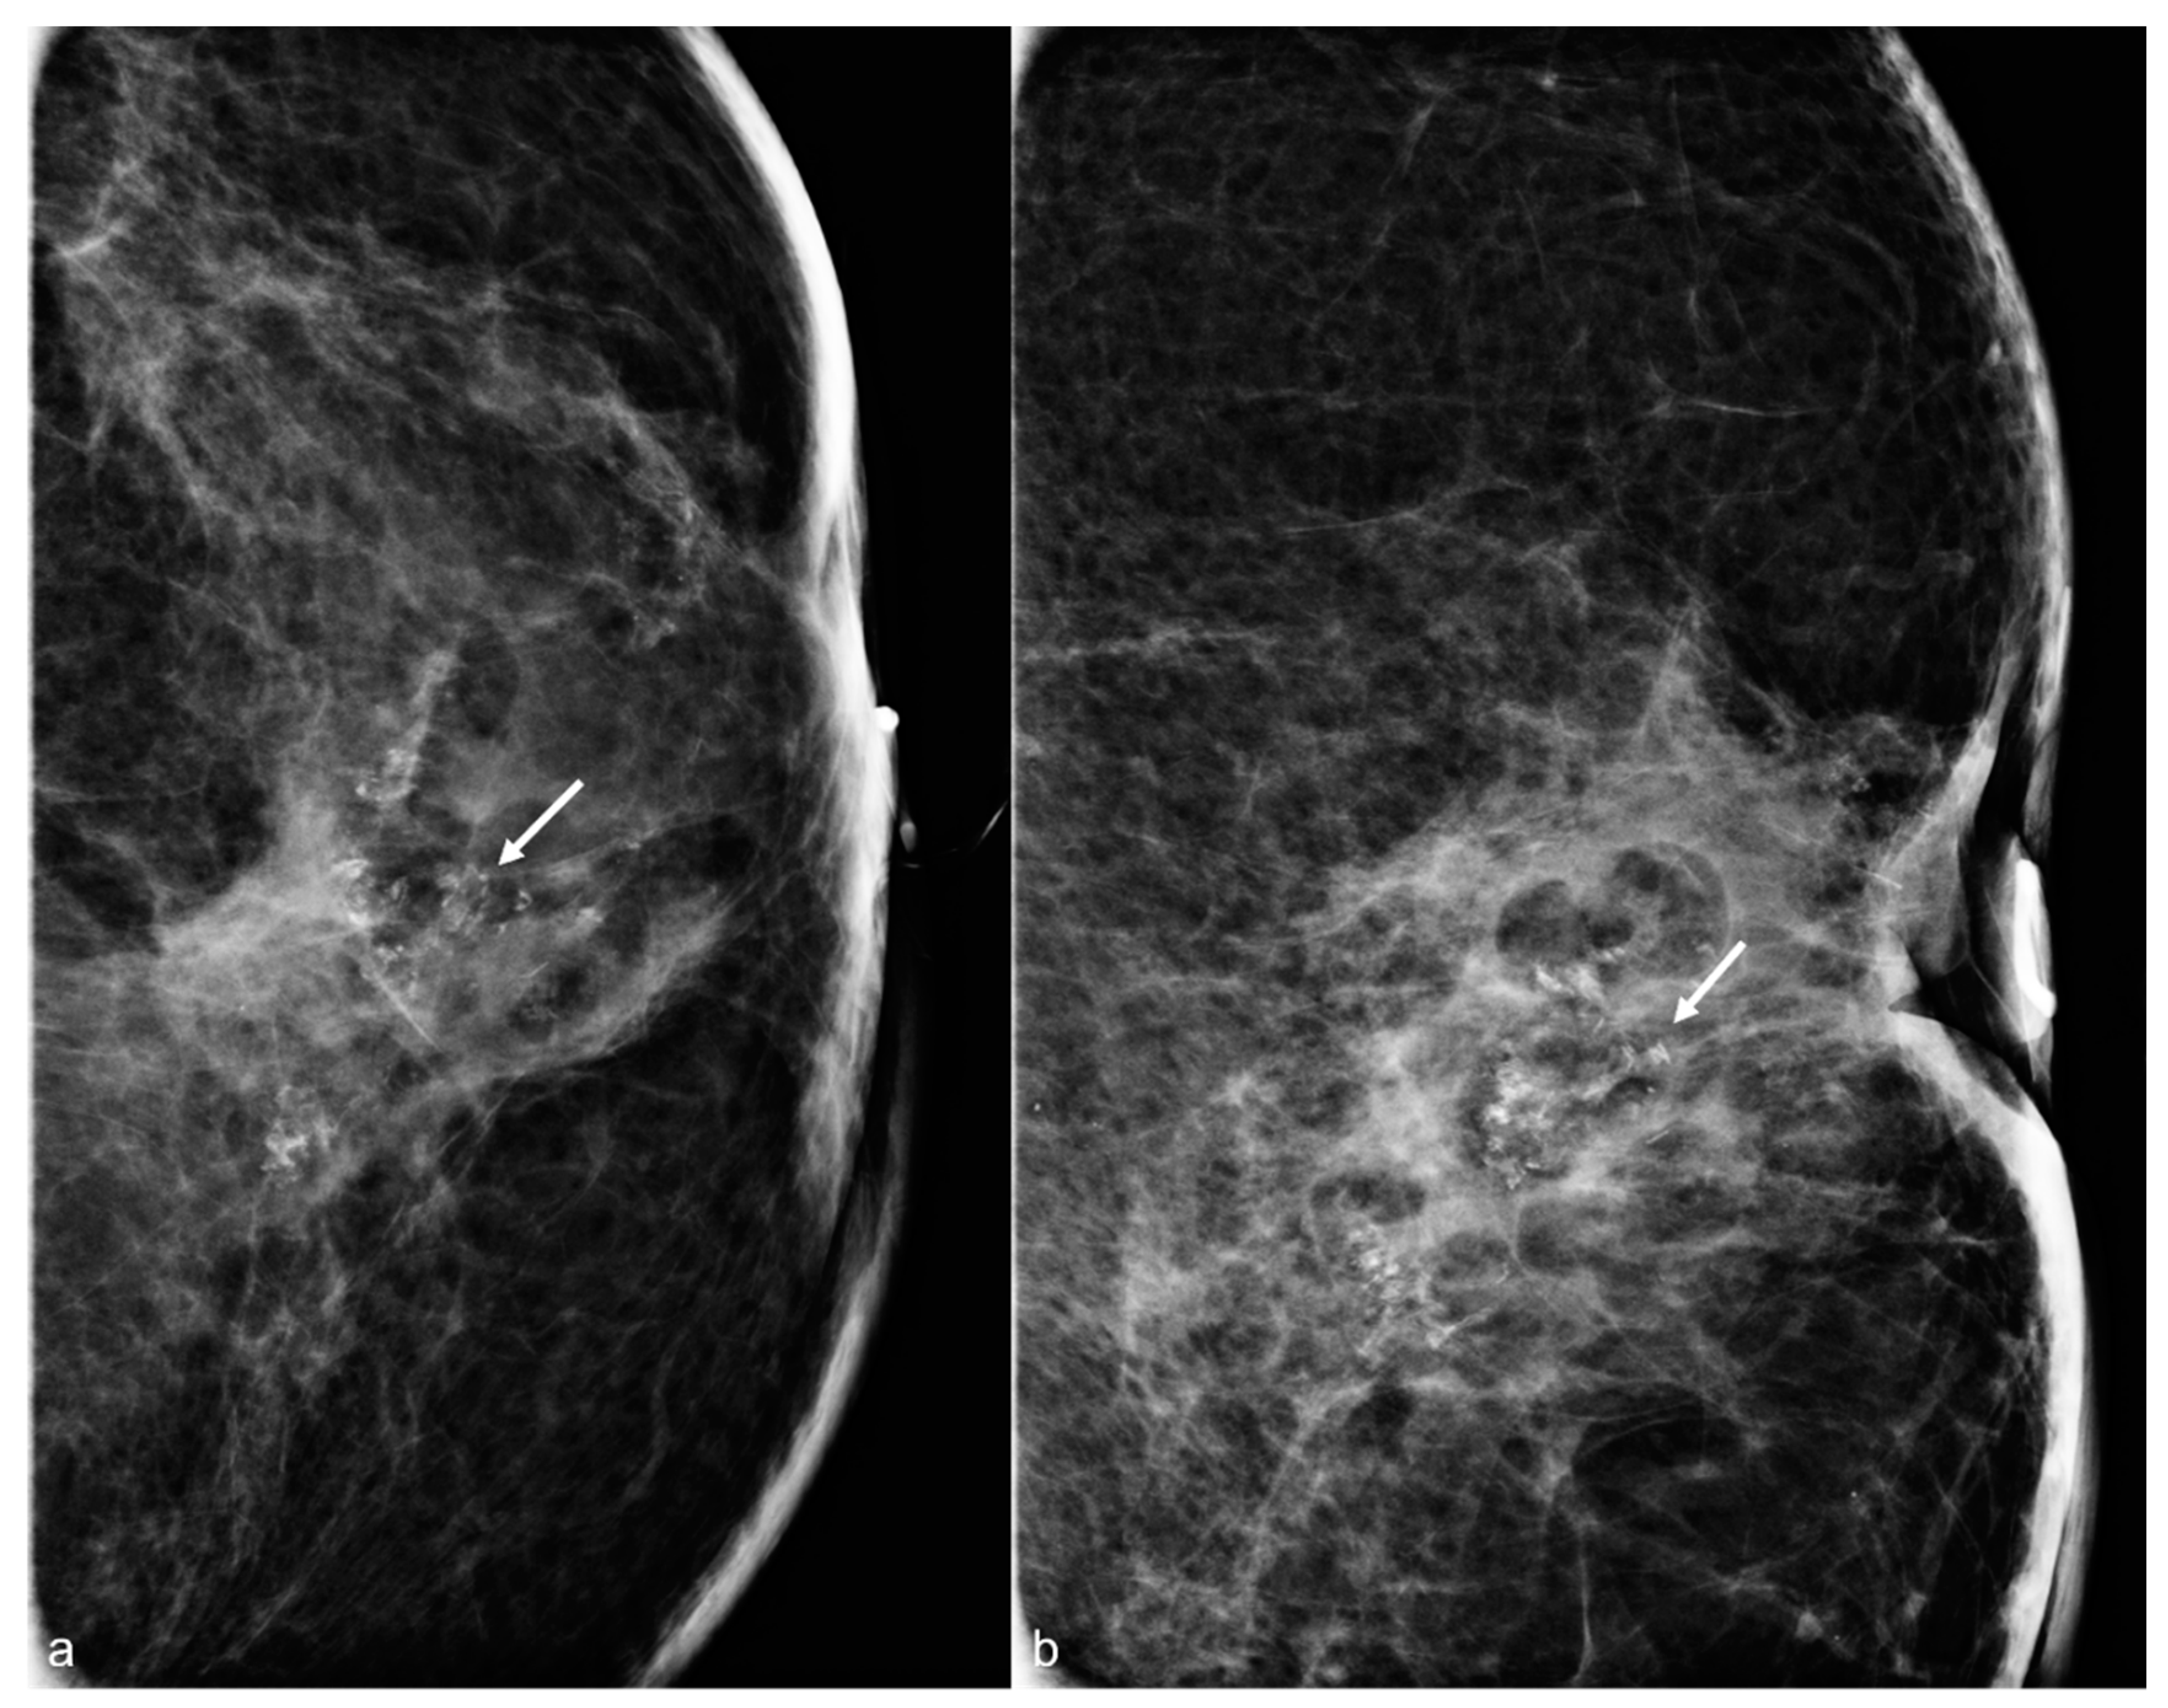

Figure 3. A 61-year-old woman had a history of subglandular silicone implants, status post BES. Surgical changes including architectural distortion (arrows) were noted in the right breast, stable for two years. ((a) Synthetic 2D MLO view from 2019; (b) 2D MLO view from 2021). The findings were consistent with post-BES change.